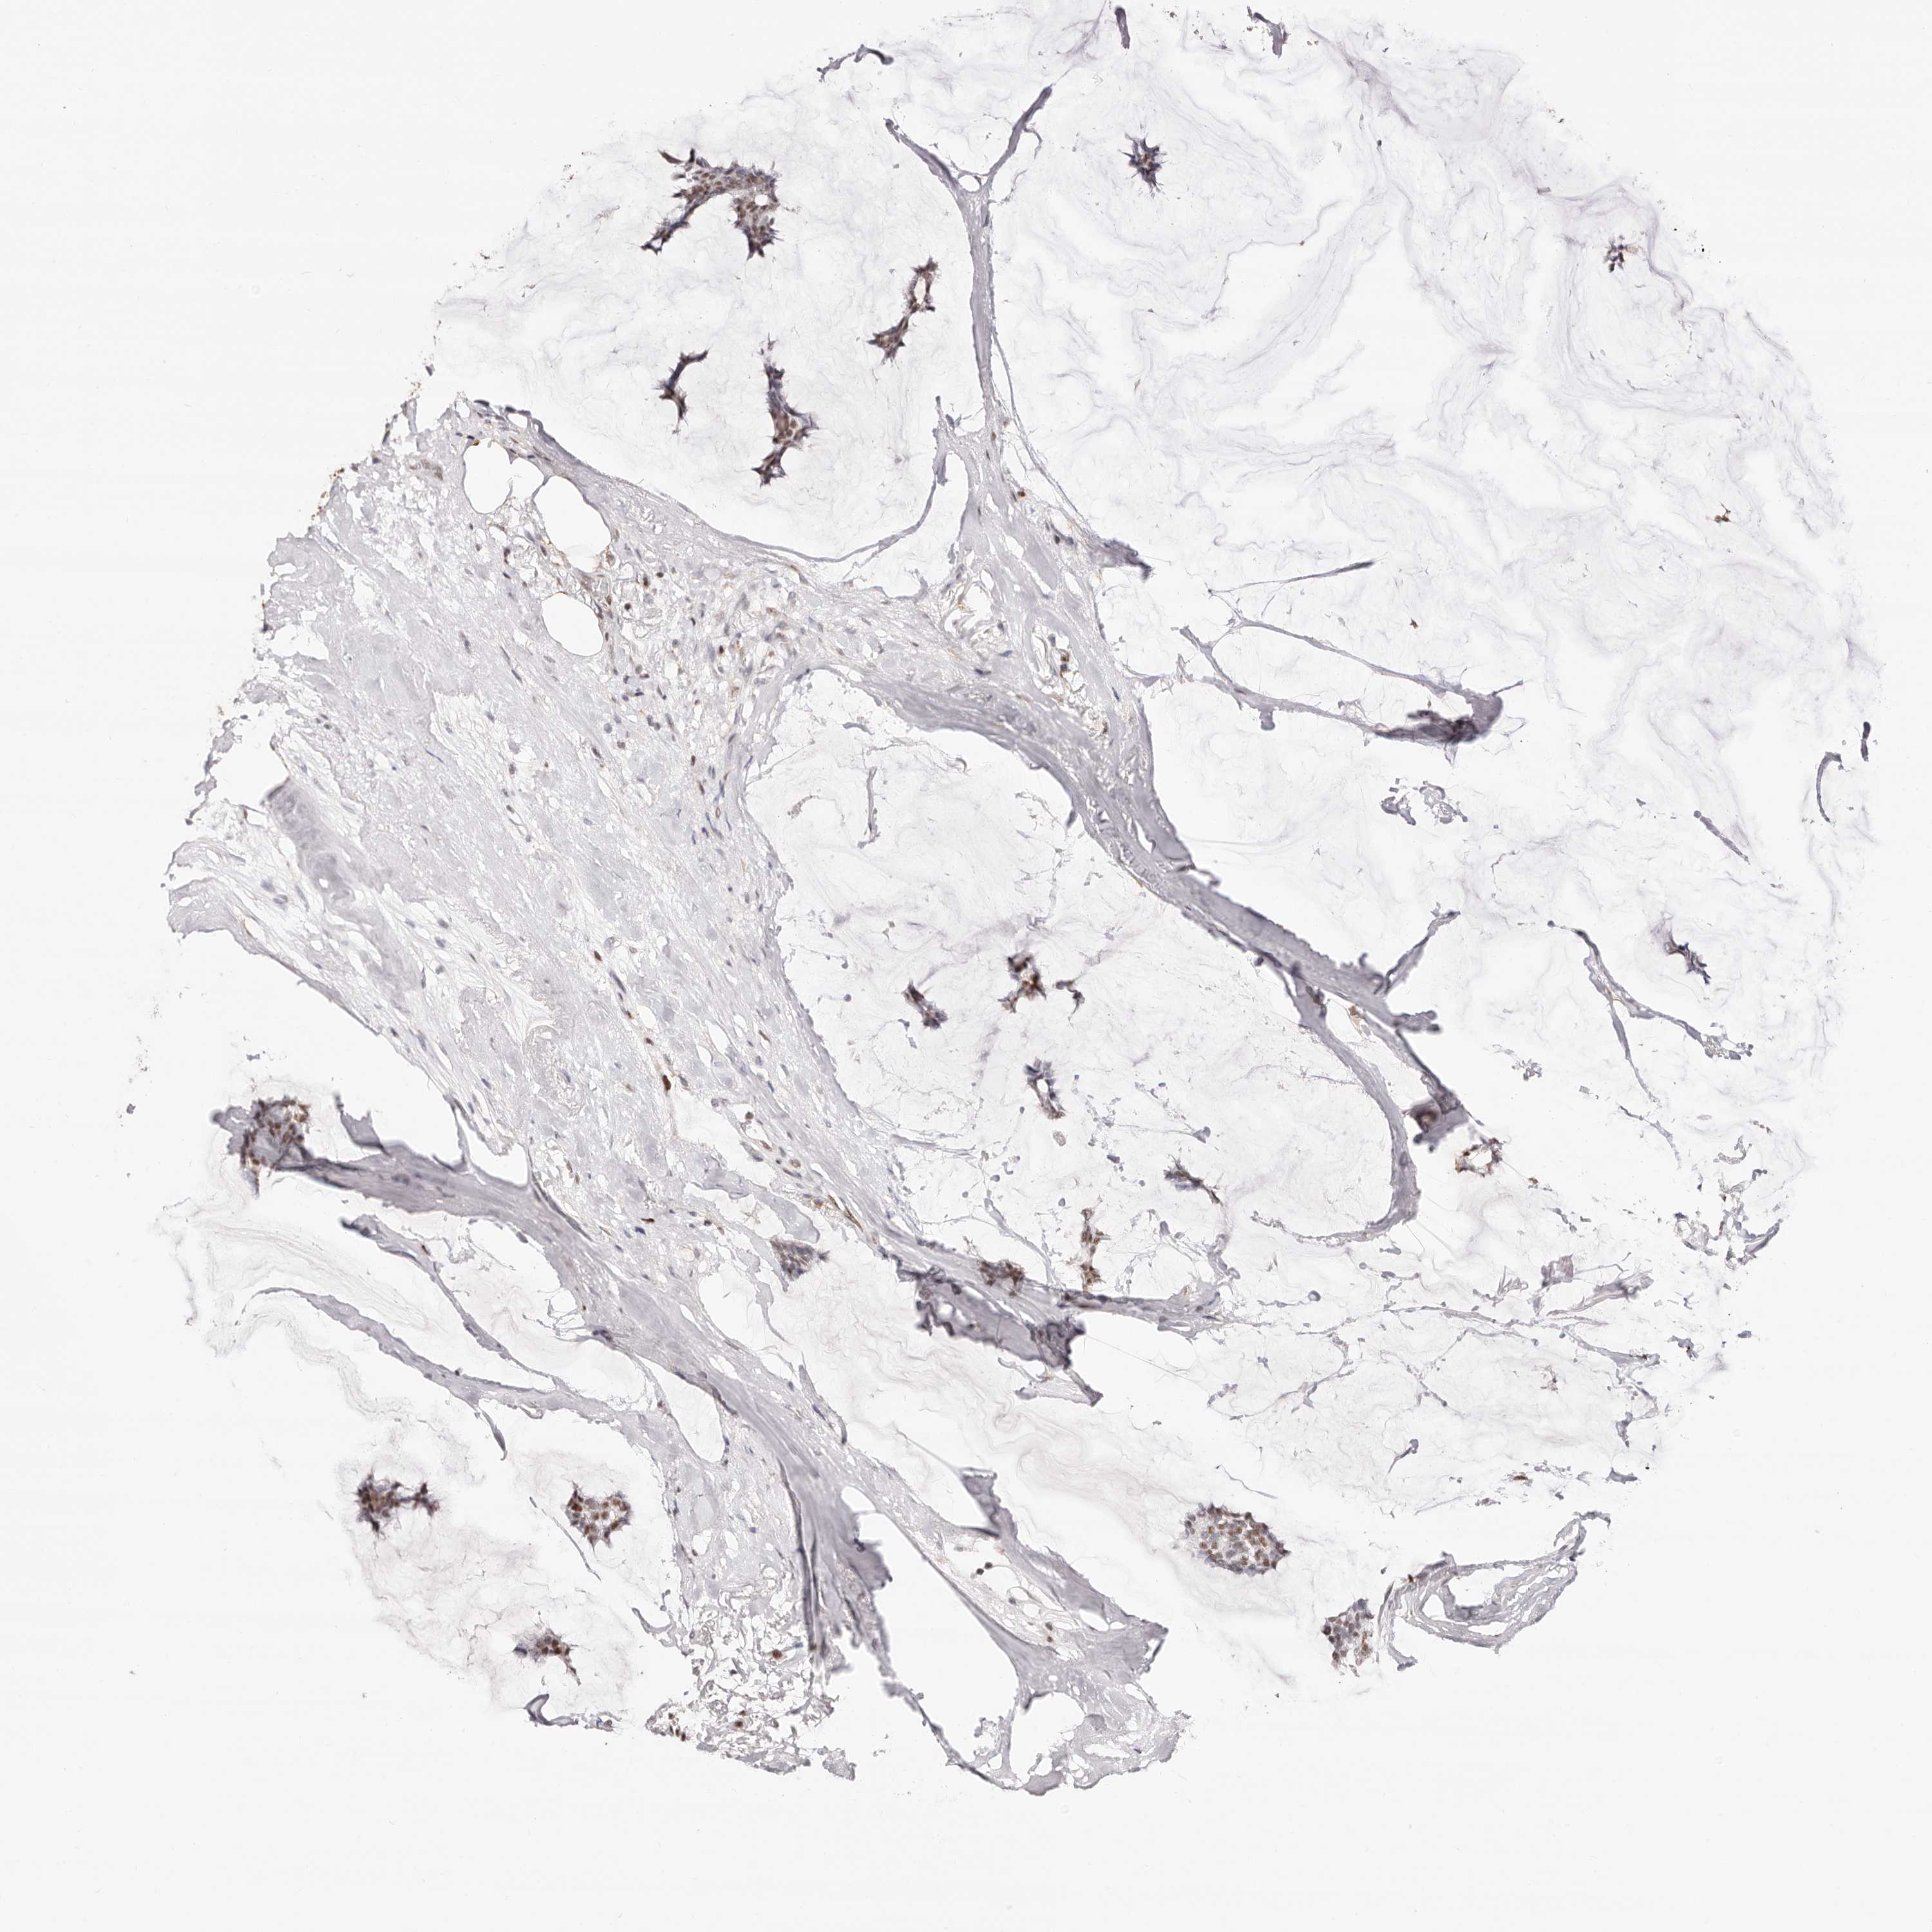

BRCA TCGA BRCA VALIDATION PROTEIN EXPRESSION